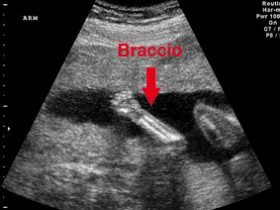

- Lo scheletro si forma.